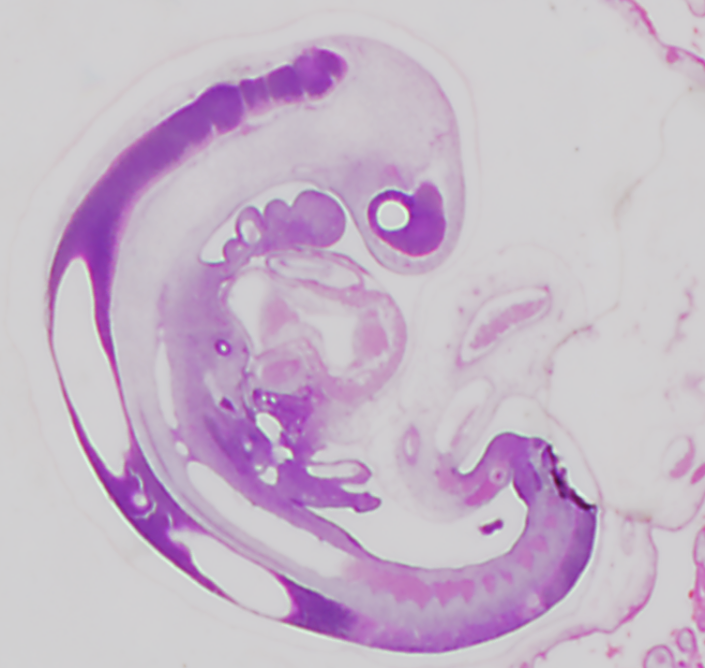

生理的臍帯ヘルニアはどのように腹腔に戻るか

「生理的臍帯ヘルニアはどのように腹腔に戻るのか」についての短報がCongenit Anomに受諾されました ヒトにおける生理的臍ヘルニアは、カーネギー期(CS)16~17週(5週)頃に始まる。この時期、一次中腸ループが胚 […]